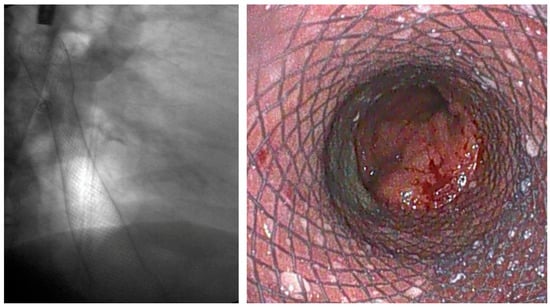

4.1.2. LAMS

Indication and Mechanism of Action

- Direct technique: puncture of the jejunal loop with a 19G needle and contrast injection to confirm position [126].

- Device-assisted EUS-GE: balloon or enteroscope passed across the stenosis to aid EUS visualization and targeting [127].

- Wireless Endoscopic Simplified Technique (WEST): described by Bronswijk et al. in 2020 and currently the most widely used technique [128], this approach involves jejunal distension via a nasoenteric tube with saline and dye, followed by “free-hand” single-step LAMS deployment under EUS guidance [128].

Efficacy and Adverse Events